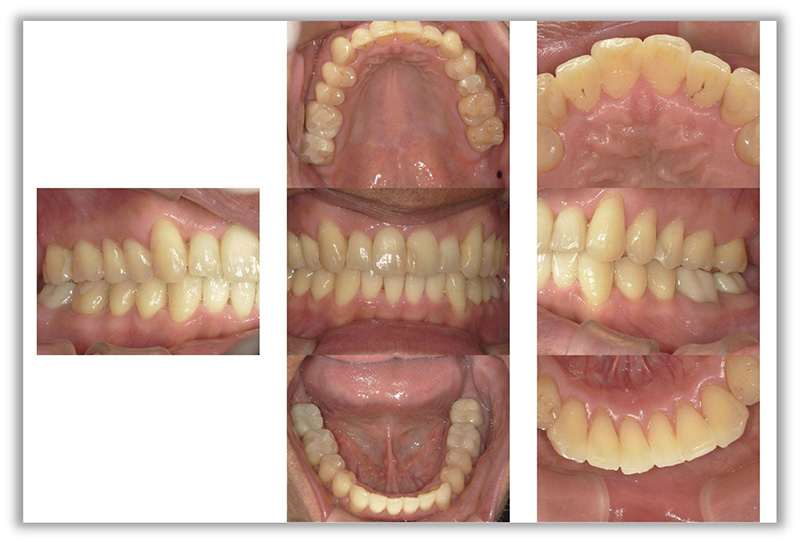

CASE_03

30代女性(インビザライン矯正)

- 患者さん情報(年齢・性別)

- 30代 女性

- 主訴

- 矯正について相談したい。前歯が出ているのがきになる。口が閉じづらい。

- 治療方法

- インビザライン矯正

- 費用

- 88万円

- 治療期間

- 約1年

- その治療によるリスク・副作用

- 歯肉退縮することがある

- 矯正中はしみたり、痛みを伴うことがある

- 患者様の声